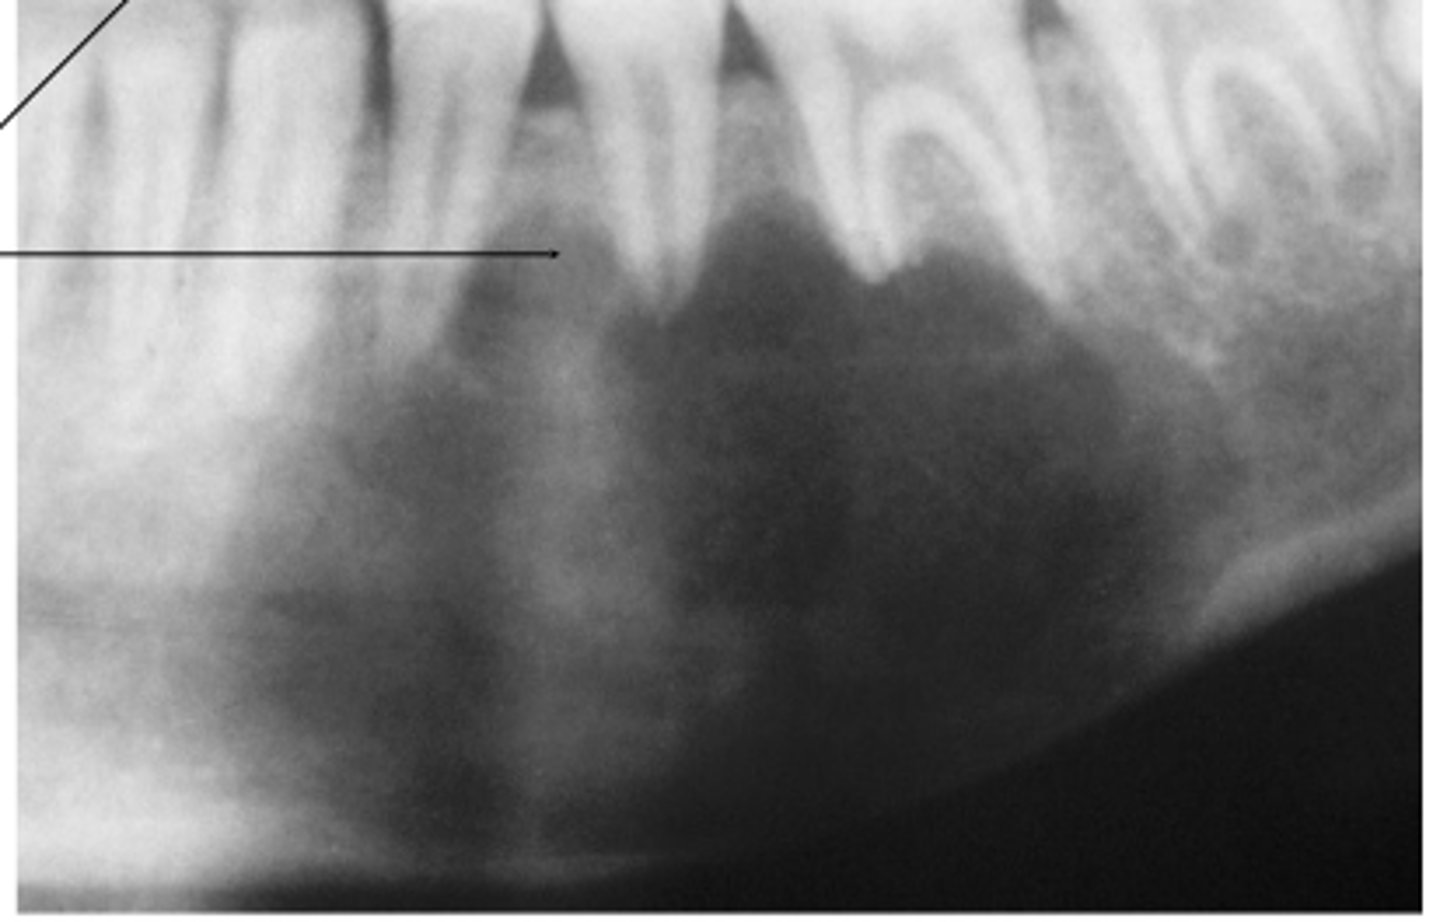

What type of lesion is a Central Giant Cell Granuloma?

An intraosseous lesion.

What is the main controversy surrounding the nature of Central Giant Cell Granuloma?

Whether it is a reactive process or a benign neoplasm.

Where is the most frequent location of Central Giant Cell Granuloma?

70% occur in the mandible

What area of the mouth is Central Giant Cell Granuloma more common?

More common in anterior portion of jaws

What are the two categories of Central Giant Cell Granuloma based on clinical and radiographic features?

Nonaggressive lesions and Aggressive lesions.

What are typical characteristics of nonaggressive Central Giant Cell Granulomas?

Relatively small, few or no symptoms, slow growth, no cortical perforation or root resorption, usually discovered during routine radiographs or due to painless jaw expansion.

How do aggressive Central Giant Cell Granulomas typically present?

Pain, rapid growth, cortical perforation, root resorption, tooth displacement, paresthesia, soft tissue extension, and mucosal ulceration.

What is the treatment for Central Giant Cell Granuloma

Thorough curettage